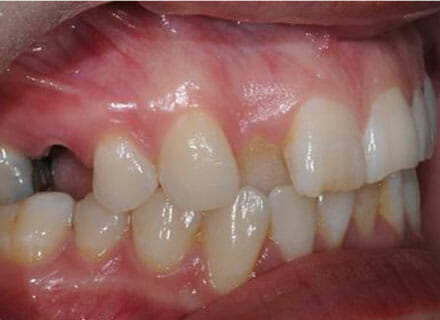

In this case the whole smile was affected by a tooth that was missing (a visible gap or hole at the side when smiling) and a tooth at the front that had grown the wrong side of the bite. We were able to correct the gap at the back by pulling the tooth behind forwards into the gap left by the previous extracted tooth. The clear brace also pushed the tooth at the front back in to the right position and the smile was massively improve. This case took around 18 months to complete.